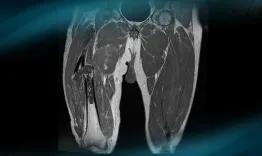

What are the therapeutic options in case of spontaneous pathological diaphyseal fracture of the right femur leading to the diagnosis of a dedifferentiated chondrosarcoma in a 52 year-old man? How would you manage this clinical case?

Dedifferentiated chondrosarcoma

Louis Courtot, Kenza Limam